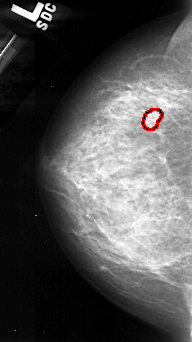

FILE: A_1097_1.LEFT_CC.OVERLAY

TOTAL_ABNORMALITIES 1

ABNORMALITY 1

LESION_TYPE CALCIFICATION TYPE PLEOMORPHIC DISTRIBUTION CLUSTERED

ASSESSMENT 4

SUBTLETY 4

PATHOLOGY MALIGNANT

TOTAL_OUTLINES 1

BOUNDARY